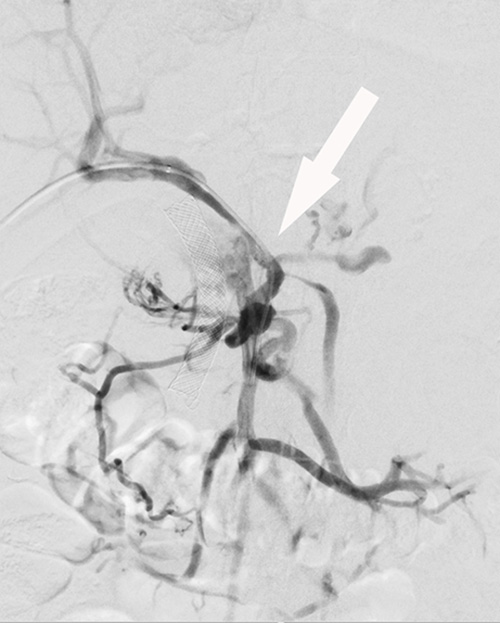

Avlastning med endoskopisk teknik av intrahepatiska gallvägar vid tumörförträngning är ofta inte möjlig, och perkutan inläggning av dränagekateter och/eller stent med interventionell radiologisk teknik är ett återstående alternativ. Perkutan rekanalisering med stent av tumöravstängd vena portae (Figur 1), eller vena lienalis, kan påtagligt reducera risken för blödning från ventrikel eller esofagusvaricer.

Figur 1. Pankreascancer. Övre bilden visar förträngd vena portae samt konfluens av vena lienalis och vena mesenterica superior (pil). Undre bilden visar vena portae (tjock svart pil), vena mesenterica superior (tunn svart pil) och vena lienalis (vit pil) öppnade med stentar.